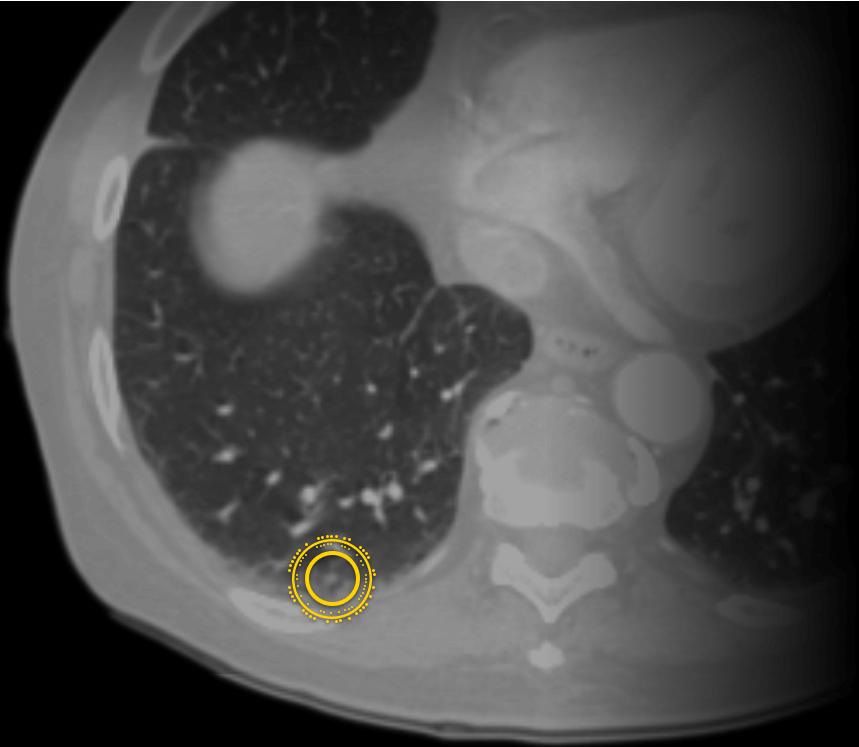

Zebra公司为患者提供基于机器学习平台的SaaS医学影像诊断分析服务Profound,让患者能够在家中快速获取准确的医学影像分析报告。这款名为“Profound”的医学影像分析软件会依据扫描件中关键的临床特征自动分析,准确率高达90%。

Zebra公司的医学影像分析可以帮助医务工作者识别出处于疾病风险期的患者,并且该网站会提供改善性的、预防性的治疗方法,用来改善患者身体状态。机器学习和深度学习的基础是大量的高质量数据,Zebra数据库已经成为全球最大的医疗影像数据库之一、全球最大的临床医学数据库之一。